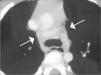

La radiografía de tórax mostró un ensanchamiento mediastínico, de contornos lisos, con un mínimo desplazamiento lateral izquierdo traqueal (fig. 1). La tomografía computarizada torácica reveló un arco aórtico elongado y tortuoso cuya porción más craneal se situaba por encima de la clavícula izquierda. También se observó un aumento de la distancia entre la arteria carótida izquierda, con origen ligeramente a la derecha de la línea media y la arteria subclavia izquierda, con origen en la aorta torácica descendente. No se identificó ninguna alteración de la secuencia y configuración de los troncos supraaórticos. La aorta descendente se situaba a la izquierda de la línea media.